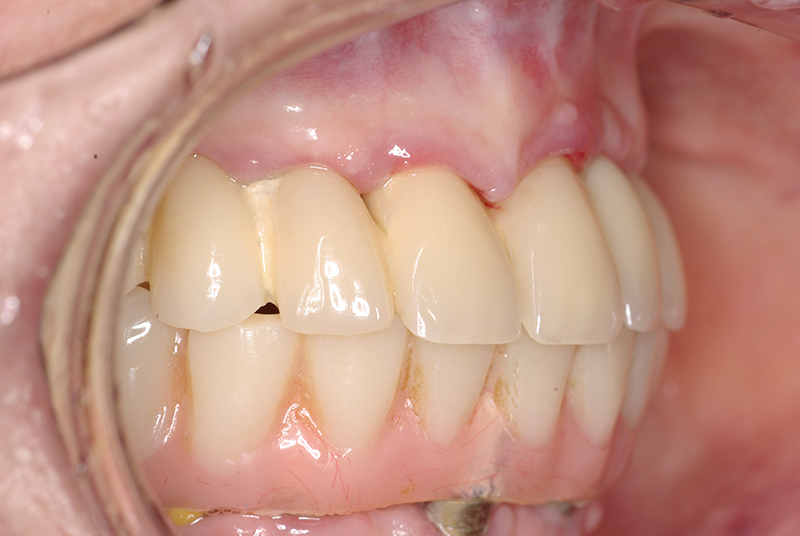

- Cirurgia de Instalação dos Implantes: Os implantes são fixados no osso maxilar ou mandibular, proporcionando uma base sólida para a prótese.

- Fixação da Prótese: Em até 72 horas após a cirurgia, a prótese provisória é instalada, permitindo que o paciente recupere a funcionalidade e a estética imediatamente.

- Conforto e Estética: A prótese provisória é funcional e visualmente semelhante aos dentes naturais.